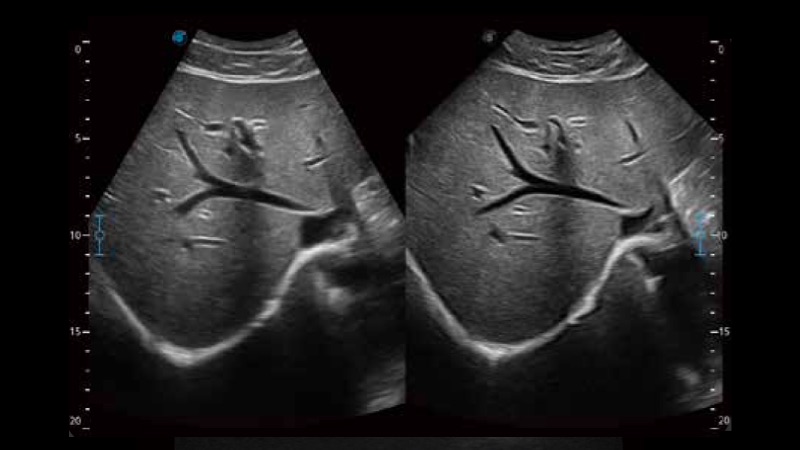

開立醫(yī)療通過不斷的技術(shù)創(chuàng)新,為大眾的生命健康提供持續(xù)關(guān)愛。P12 Plus采用全新一代超聲成像平臺,新平臺旨在將真實(shí)還原組織解剖結(jié)構(gòu)作為首要目標(biāo)。平臺采用全新集成化硬件模塊,搭載新一代芯片,系統(tǒng)性能得到大幅提升,為您的診斷提供了豐富的臨床信息。優(yōu)異的圖像表現(xiàn),豐富的探頭配置,全面的應(yīng)用功能,為您日常診斷提供了可靠的助手。

P12 Plus

彩色多普勒超聲診斷系統(tǒng)